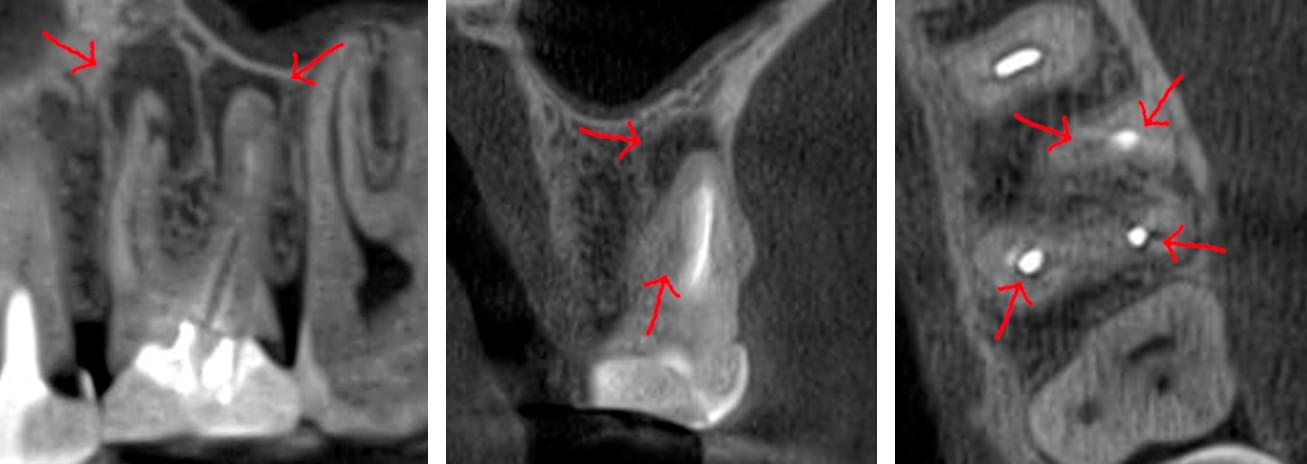

Зуб — це не просто монолітний об'єкт, а складна система мікроканалів. На плоскому 2D-знімку вони часто перекривають один одного, створюючи ілюзію простої анатомії.

Непомічений канал — це джерело майбутньої інфекції та причина «загадкового» болю після лікування. Завдяки високій роздільній здатності обладнання MyRay, лікар бачить кожен мікронний канал ще до того, як візьме до рук інструмент.

Коли коріння «ховає сюрпризи» - Корені зубів часто мають складну кривизну, гачкоподібні закручення або розгалуження, які на звичайному 2D-знімку накладаються один на одного, створюючи ілюзію прямого каналу. На плоскій картинці неможливо побачити реальний об'єм та напрямок вигину, що критично важливо при видаленні «зубів мудрості» або ендодонтичному лікуванні. КТ MyRay дає змогу лікарю заздалегідь побачити 3D-геометрію кожного кореня, оцінити його близькість до нижньощелепного нерва чи гайморової пазухи та підібрати правильну тактику роботи. Це мінімізує ризики поломки інструменту в каналі або травмування сусідніх структур, перетворюючи складну хірургію на прогнозовану процедуру.